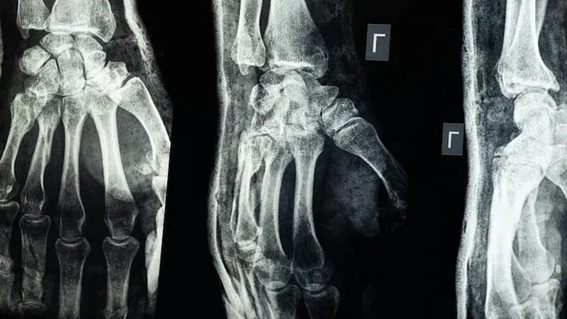

Hoje, fraturas graves exigem placas e parafusos metálicos, seguidos de uma segunda cirurgia para retirá-los — processo caro, demorado e sujeito a infecções.

O Bone-02 promete encurtar esse caminho. Testados em mais de 150 pacientes, o medicamento suportou mais de 180 kg de pressão.